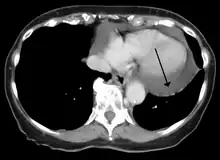

Cardiac CT and MRI scans: cross-sectional imaging with computed tomography (CT) can help localize and quantify the effusion, especially in a loculated effusion (an effusion contained to one area).[12] CT imaging also helps assess for pericardial pathology (pericardial thickening, constrictive pericarditis, malignancy-associated pericarditis).[1] Whereas cardiac MRI is reserved for patients with poor echocardiogram findings and for assessing pericardial inflammation, especially for patients with continued inflammation despite treatment.[5] CT and MRI imaging can also be used for continued follow up on patients.

A CT scan showing a pericardial effusion